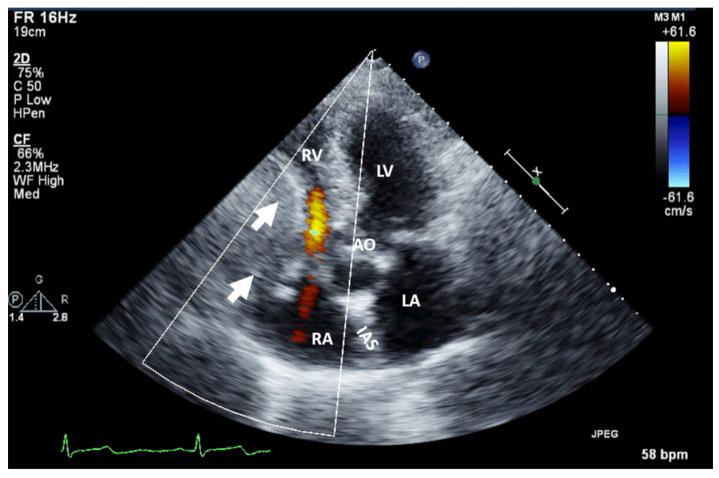

A right heart tumor can be identified by transthoracic echocardiography during a routine examination or due to cardiac symptoms. The first step is the assessment by echocardiography, with its multiple techniques, and the obtained information must be judged in a clinical and biological context. The second step comprises one, sometimes even two, of the more complex modality imaging methods. The choice is driven not only by the advantages of each imaging technique but also by local expertise or the preferred imaging modality in the center. This step is followed by staging, follow-up, and/or imaging-guided excision or biopsy, which is performed in selected cases in order to obtain anatomopathological confirmation. In the presence of features suggestive of malignancy or causing hemodynamic impairment, a transvenous biopsy is essential before the more complex imaging modalities (which are still relevant in the staging process). Using a structured imaging approach, it is possible to reach an appropriate diagnosis without a biopsy. Frequently, these imaging techniques have a complementary role, so an integrated imaging approach is recommended. This proposed algorithm for appropriate diagnosis of right heart tumors could serve as a practical guide for clinicians (not only imaging specialists).

右心肿瘤可在常规检查期间或因心脏症状通过经胸超声心动图得以识别。第一步是采用多种技术进行超声心动图评估,且必须在临床和生物学背景下对所获信息进行判断。第二步包括一种,有时甚至是两种更为复杂的影像学检查方法。其选择不仅取决于每种成像技术的优势,还取决于当地的专业水平或该中心首选的成像方式。此步骤之后是分期、随访和/或成像引导下的切除或活检,在特定病例中进行这些操作以获得解剖病理学确认。若存在提示恶性或导致血流动力学损害的特征,则在采用更复杂的成像方式(在分期过程中仍具有相关性)之前,经静脉活检至关重要。采用结构化成像方法,无需活检也有可能做出恰当诊断。这些成像技术常常具有互补作用,因此建议采用综合成像方法。这种针对右心肿瘤恰当诊断的提议算法可为临床医生(不仅是影像专家)提供实用指南。